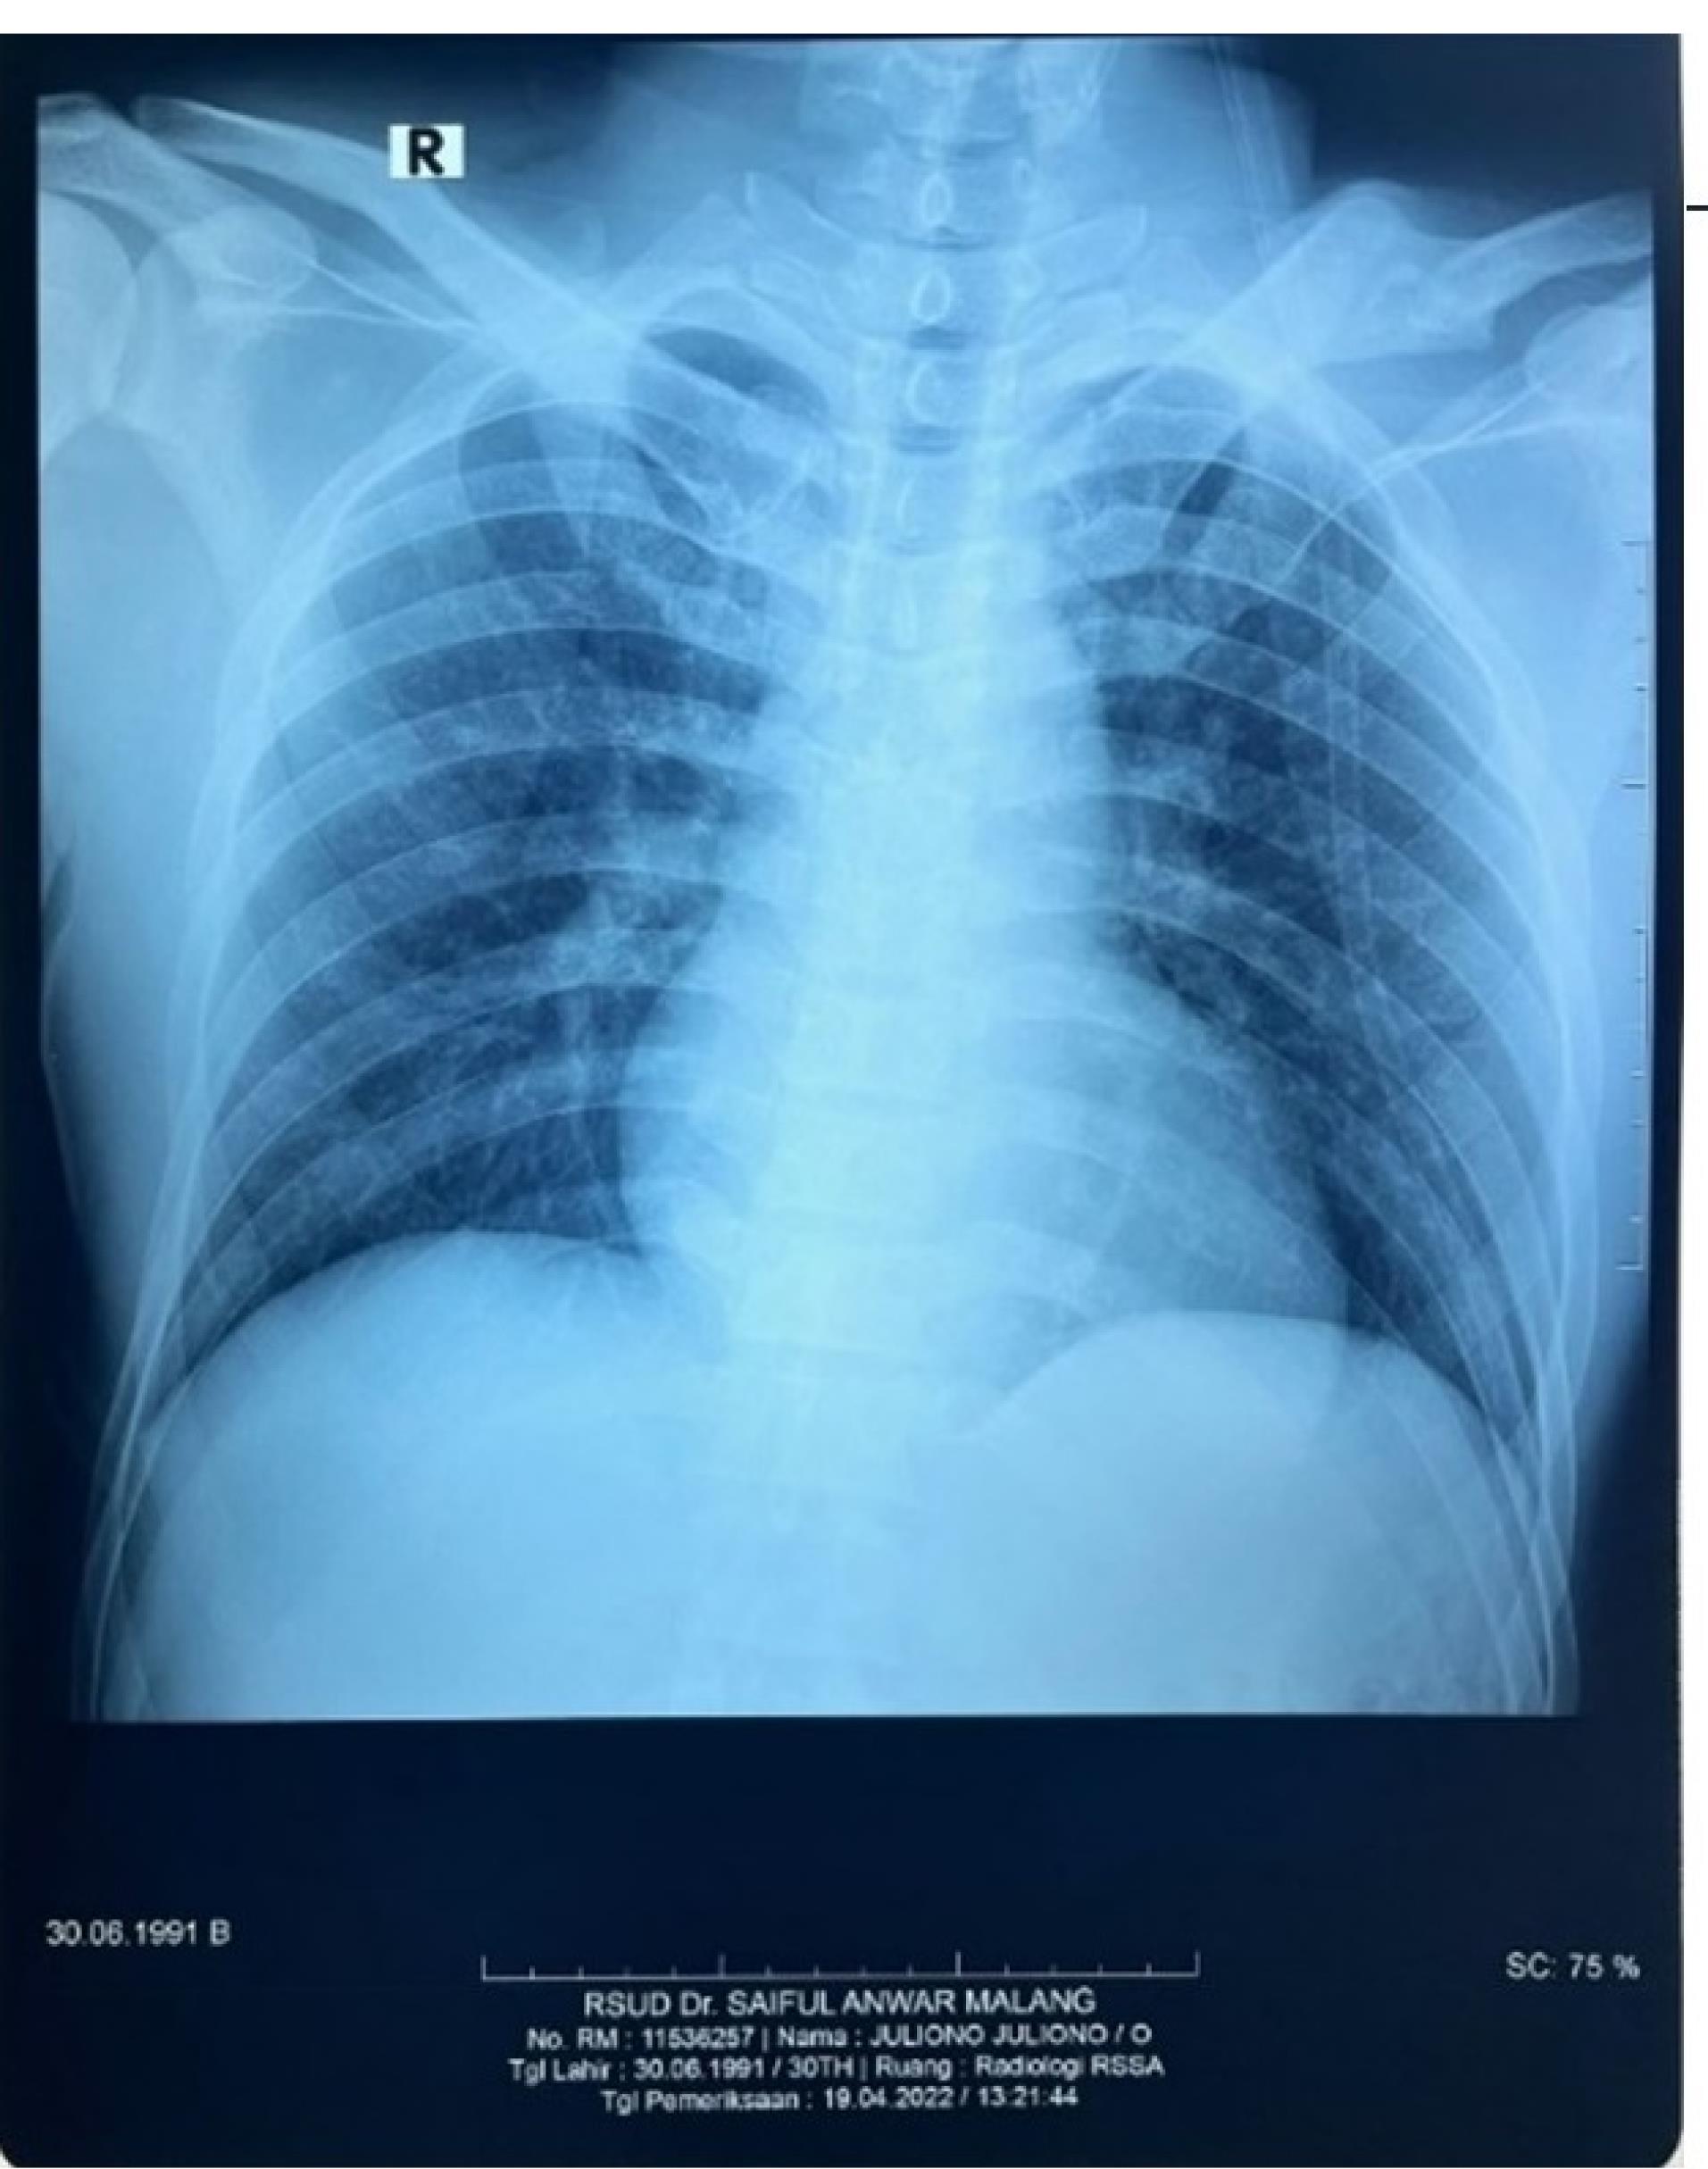

The result of diagnosis stated that the patient had convulsion, CVA ICH frontoparietal D vol 18 cc and stage I hypertension. There was no aneurism or AVM (Figure 3). All procedures performed in this study were in accordance with the ethical standards of the institutional and/or national research committee.

Figure 3.

Head CT angiography